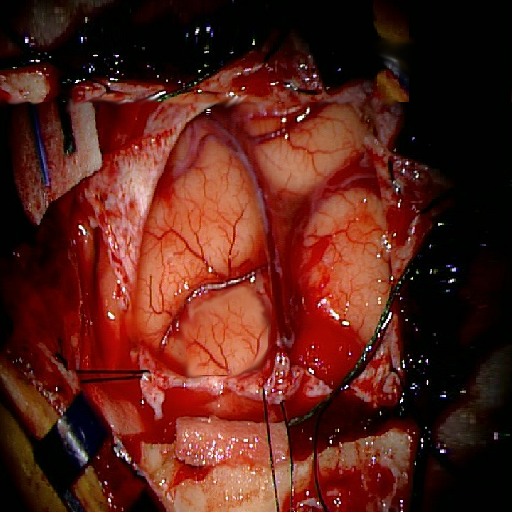

We tested our method retrospectively on 6 clinical datasets from 6 patients (cases) (see Fig. 5). These consisted of preoperative T1 contrast MRI scans and intraoperative images of the brain surface after dura opening. Cortical vessels around the tumors were segmented and triangulated to generate 3D meshes using 3D Slicer. We generated 100 poses for each 3D mesh (i.e.: each case) and used a total of 15 unique textures from human brain surfaces (different from our 6 clinical datasets) for synthesis using . In order to account for potential intraoperative brain deformations [4] we augment the textured projection with elastic deformation [21] resulting in approximately 1500 images per case. The surgical images of the brain (left image of the stereoscopic camera) were acquired with a Carl Zeiss surgical microscope. The ground-truth poses were obtained by manually aligning the 3D meshes on their corresponding images.

Fig. 5 shows our results as Augmented Reality views with bounding boxes and overlaid meshes. Our method produced visually consistent alignments for all 6 clinical cases without the need for initial registration. Because our current method does not account for brain-shift deformation, our method produced some misalignment errors. However, in all cases, our predictions are similar to the ground truth.